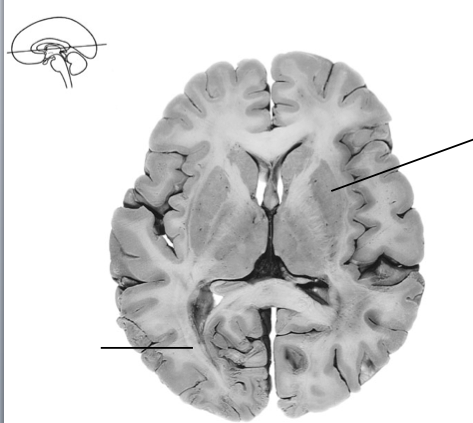

calcarine sulcus

light yellow

primary visual cortex

Pink area

Primary Visual cortex (V1, area 17)

optic tract

visual radiation